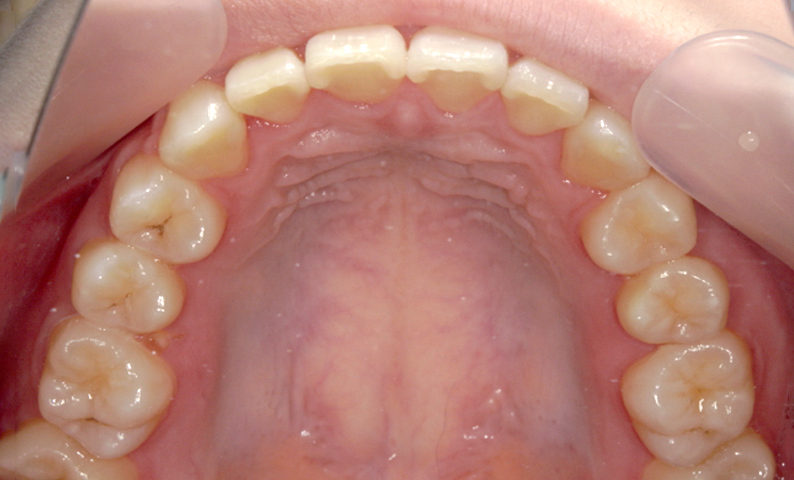

症例_004 上顎だけの部分矯正

治療期間:6ヶ月金額:27万円+税男性出っ歯上の前歯だけ

| Before | After |